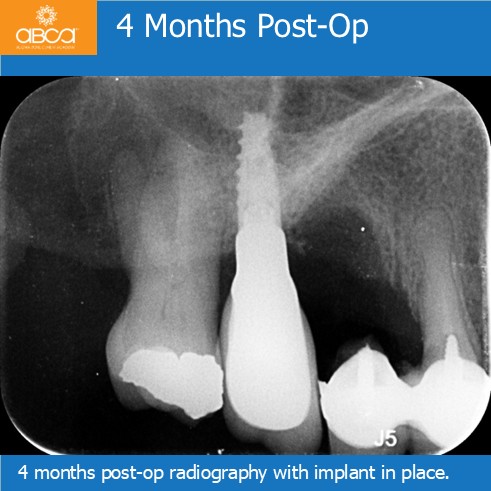

Initial CBCT images show the estimated ridge height as 1-2 mm below the sinus. The B.Y.2 diamond milling bur breaks through the sinus floor. Following the Augma Lift™ technique protocol, membrane elevation and augmentation are performed. Radiography shows implant placement 4 months post-op in newly formed bone.